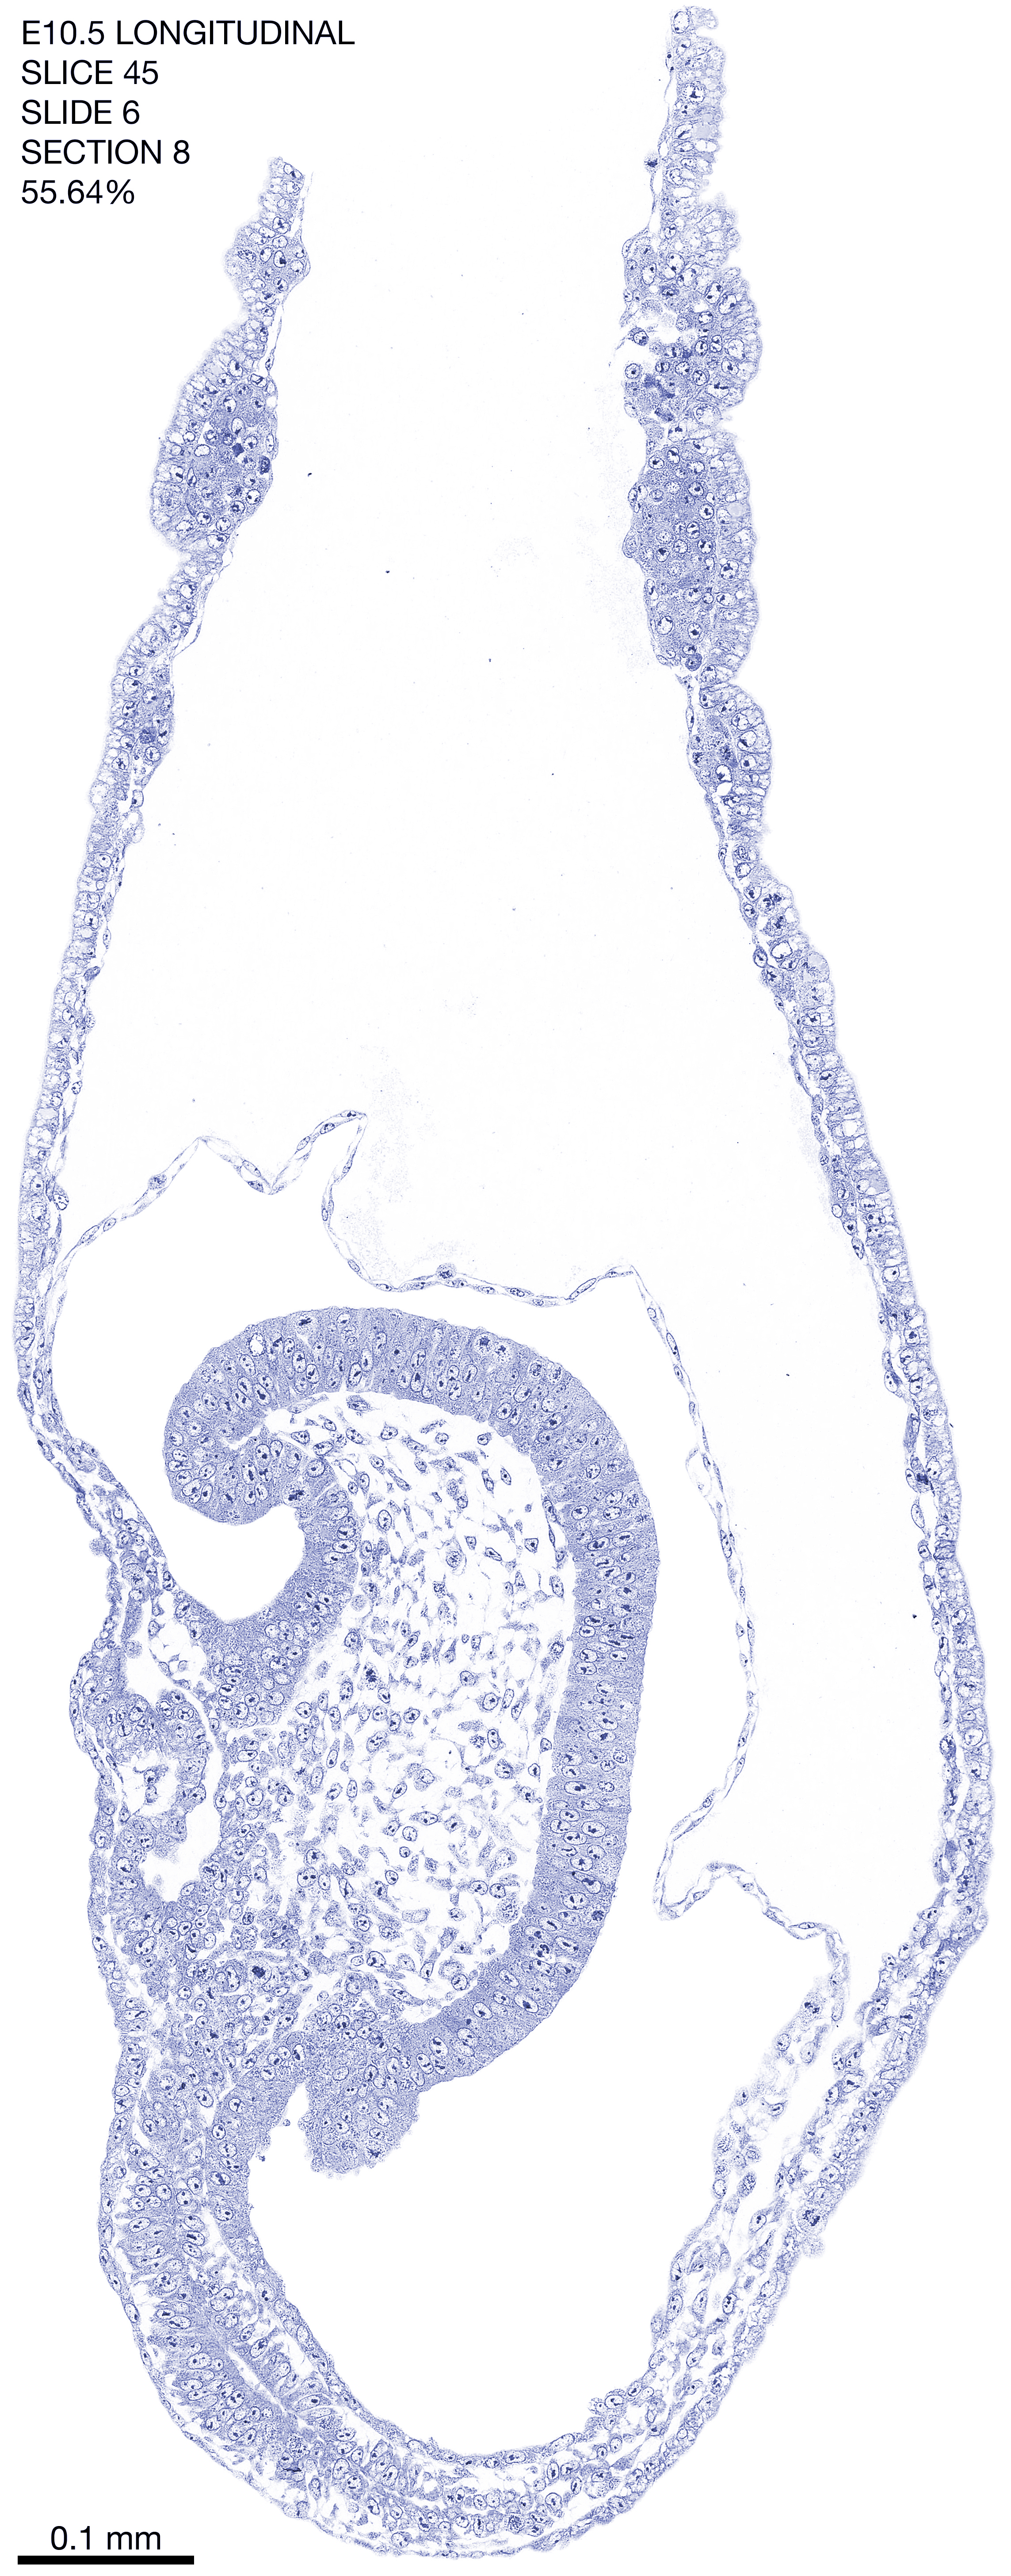

E10.5 Longitudianal Archive This page contains jpg files of ALL SLICES (each 3µm thick) that were scanned of the E10.5 longitudinally cut specimen. Download: Large | High Res Download: Large | High Res Download: Large | High Res Download: Large | High Res Download: Large | High Res Download: Large | High Res Download: Large | High Res Download: Large | High Res Download: Large | High Res Download: Large | High Res Download: Large | High Res Download: Large | High Res Download: Large | High Res Download: Large | High Res Download: Large | High Res Download: Large | High Res Download: Large | High Res Download: Large | High Res Download: Large | High Res Download: Large | High Res Download: Large | High Res Download: Large | High Res Download: Large | High Res Download: Large | High Res Download: Large | High Res Download: Large | High Res Download: Large | High Res Download: Large | High Res Download: Large | High Res Download: Large | High Res Download: Large | High Res Download: Large | High Res Download: Large | High Res Download: Large | High Res Download: Large | High Res Download: Large | High Res Download: Large | High Res Download: Large | High Res Download: Large | High Res Download: Large | High Res Download: Large | High Res Download: Large | High Res Download: Large | High Res Download: Large | High Res Download: Large | High Res Download: Large | High Res Download: Large | High Res Download: Large | High Res Download: Large | High Res Download: Large | High Res Download: Large | High Res Download: Large | High Res Download: Large | High Res Download: Large | High Res Download: Large | High Res Download: Large | High Res Download: Large | High Res Download: Large | High Res